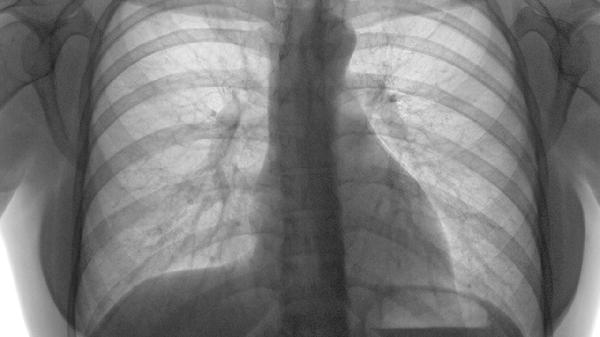

对于严重移位性骨折或合并内脏损伤者,需行胸骨钢板内固定术或钢丝环扎术。术后需住院观察1-2周,定期复查X线评估愈合情况。手术干预能有效恢复胸廓稳定性,降低畸形愈合风险。